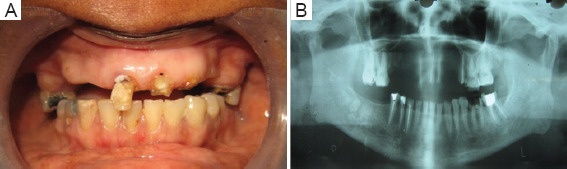

Case presentation: A 41-year-old female presented with a history of difficulty in chewing and poor appearance. Examination revealed that the patient had missing teeth in the maxilla (12, 13, 14, 15, 23, and 24), in the mandible (46 and 47), and in teeth 11, 21, 22, 25, 36, 37, 43, 44, and 45 were root canal treated, of which 21, 22, and 25 did not have any coronal structure and 36 had a discharging sinus. The periodontal condition of the remaining teeth was good and the vertical dimension was reduced. This patient had multiple missing and badly damaged anterior teeth. Hence, Hobo and Takayama twin stage method was used to re-establish the anterior guidance for full mouth rehabilitation.